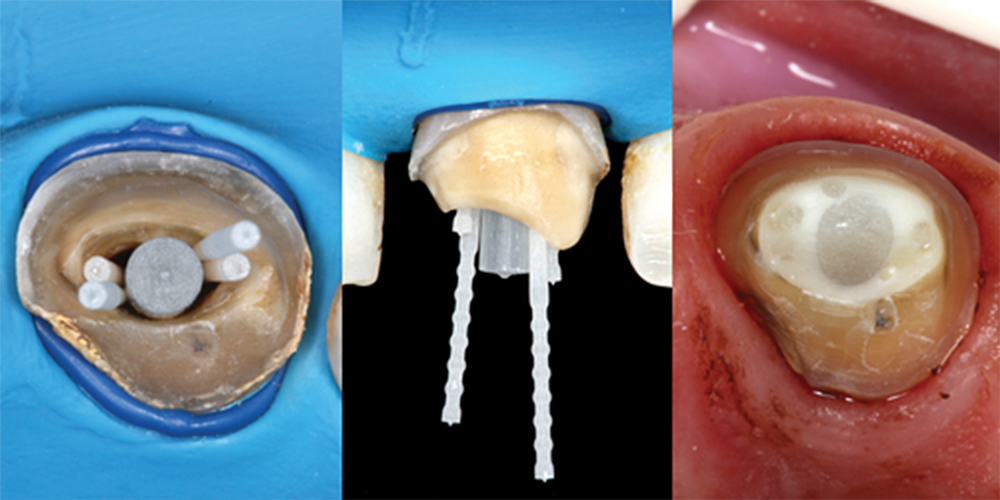

(6.) Occlusal and buccal views showing placement of accessory posts and occlusal view of the completed buildup.

Figure 6

Accessory Fiber Posts

Also referred to in the literature as auxiliary posts, accessory posts are thin fiber tendrils or, in essence, "mini" fiber posts (eg, Fibercone®, RTD Dental; Reforpin®, Angelus; UniCore®, Ultradent). They are designed to be used alongside a master post to displace the cement with a precured, factory-made composite material. Similar to auxiliary gutta percha cones, they can be inserted into the cement as needed (Figure 6). Studies show that accessory fiber posts minimize cement thickness,15 reduce stress on internal surfaces,16 and increase the tooth's resistance to fracture.17 This is a versatile and effective technique, but it requires the ability to conscientiously and rapidly place posts and adds to the cost of the restoration.